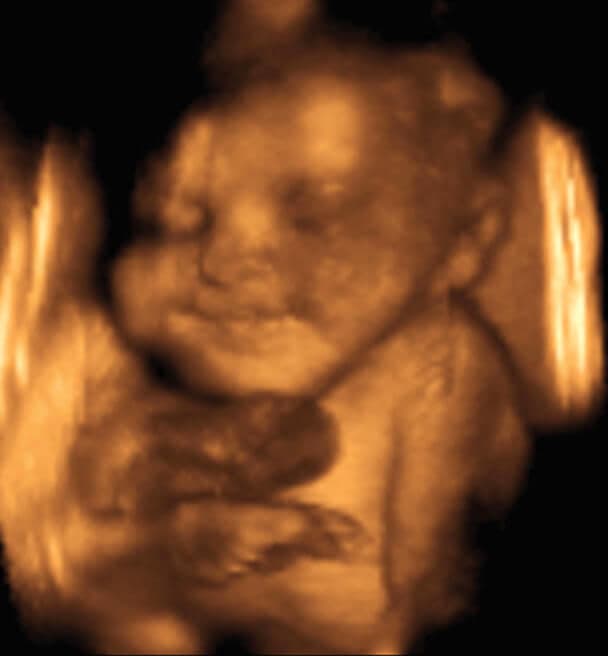

32 weeks and 3 days pregnant

Published: 29 Aug 2016